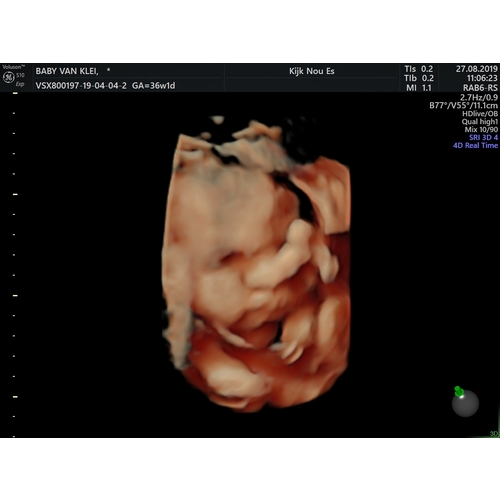

Als je op de Facebook pagina van Kijk Nou Es gaat kijken dan zie je met hoeveel weken hun een 3D echo hebben gedaan. Sommige zijn ook met de 38 weken en die waren echt mooi. Het ligt natuurlijk aan hoe je baby ligt en of die mee wilt werken 😅

Ik heb het gedaan met 32 weken en bij de vk met 36.0.. prachtig beeld, kon hem zo goed zien!